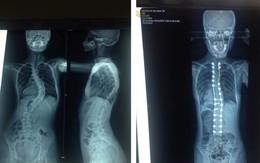

Phẫu thuật chỉnh hình cột sống 'uốn lượn' của thiếu nữ 15 tuổi

TTO - Lần đầu tiên tại ĐBSCL, một nữ bệnh nhân đã được Bệnh viện Quân y 121 (Quân khu 9) phẫu thuật chỉnh hình vẹo cột sống từ ngực đến thắt lưng thành công.

Bị vẹo cột sống đến 70 độ do hội chứng Marfan

TTO - Sau 2 năm kể từ khi phát hiện bị cong vẹo cột sống, em G.N. (15 tuổi, ngụ TP.HCM) bị vẹo đến 70 độ. Tại Bệnh viện Trưng Vương, TP.HCM, các bác sĩ cho biết em mắc hội chứng Marfan.